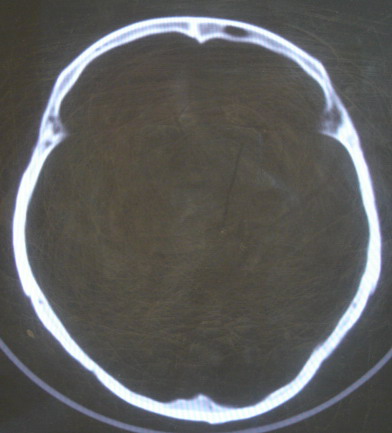

女 63岁 左额部碰伤

现有资料未见骨折表现

左枕部颅缝略增宽并轻度错位,建议结合临床,必要时复查

未见明显骨折

未见异常.

未经高分辩率处理。未见明显异常。

左额部未见明确骨折

左侧颞枕部颅缝分离骨折可疑。建议结合临床,必要时复查。

都错位了,当然是报骨折了。

左侧颞枕部颅缝分离骨折可疑。

结合临床,排除左侧颞枕部颅缝分离骨折可能。